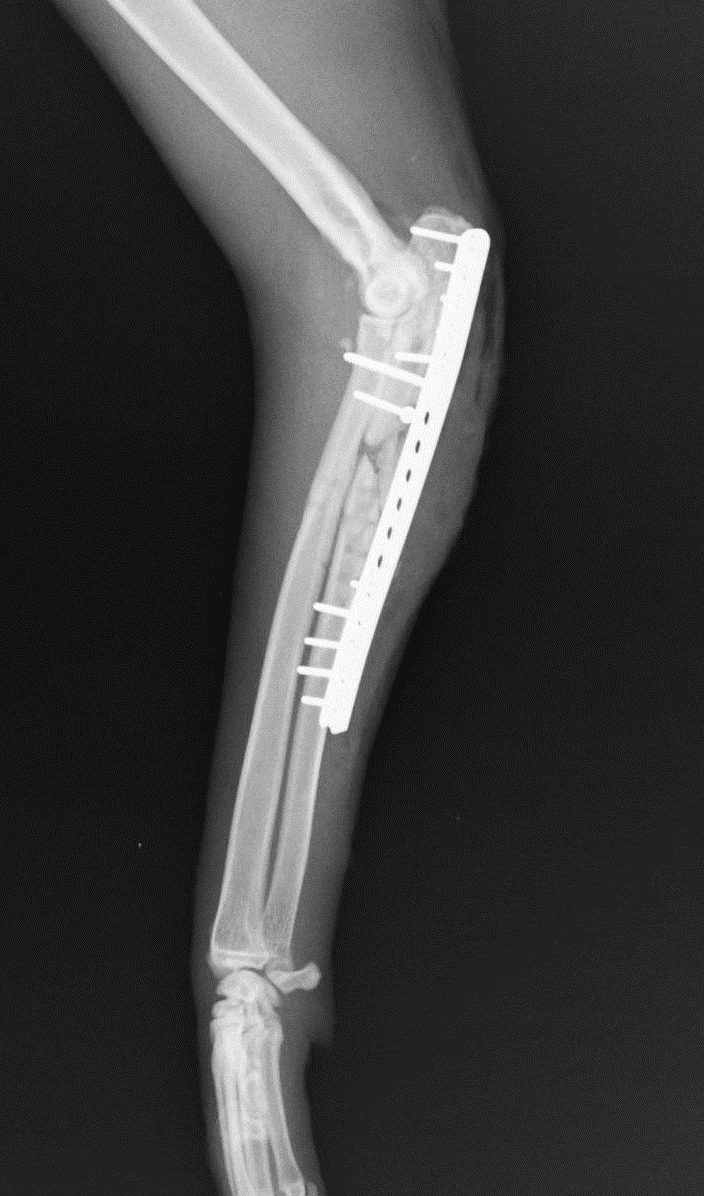

そのため手術により、インプラント(体内に埋め込むプレートなどの医療用人工素材)を除去し、解剖学的に正しい位置に整復したうえでプレート・スクリューによる再固定を行いました。

手術後のレントゲン画像です。一枚のプレートと複数のスクリューにより固定され、外貌も自然な状態になりました。また骨癒合を促すため、骨折部には海綿骨移植を実施しました。

後日、骨が癒合したのを確認し、インプラントを除去して完治しました。